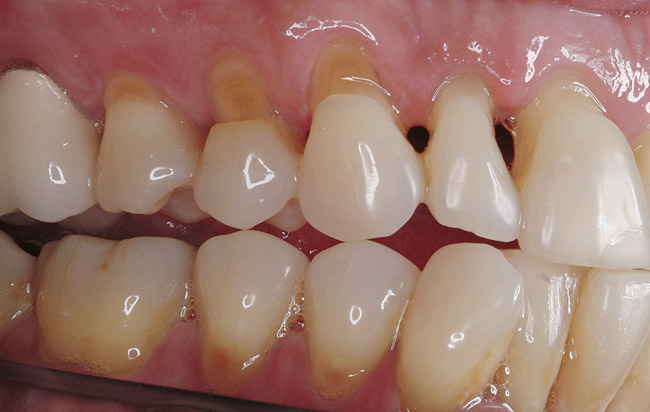

Replacement of existing restorations is responsible for 75% of all operative dentistry.15,19 The reasons for placement and replacement of restorations of direct restorative materials include: primary caries (Figure 1 and Figure 2); recurrent caries (Figure 3); poor margins (Figure 4 and Figure 5); restoration fracture (Figure 6 and Figure 7); tooth fracture (Figure 8); esthetics (Figure 9); non-carious tooth structure lost (attrition, abrasion, abfraction, erosion) (Figure 10); and pain/sensitivity.

Figure 10  Non-carious cervical lesions are evident in both arches.

Figure 10